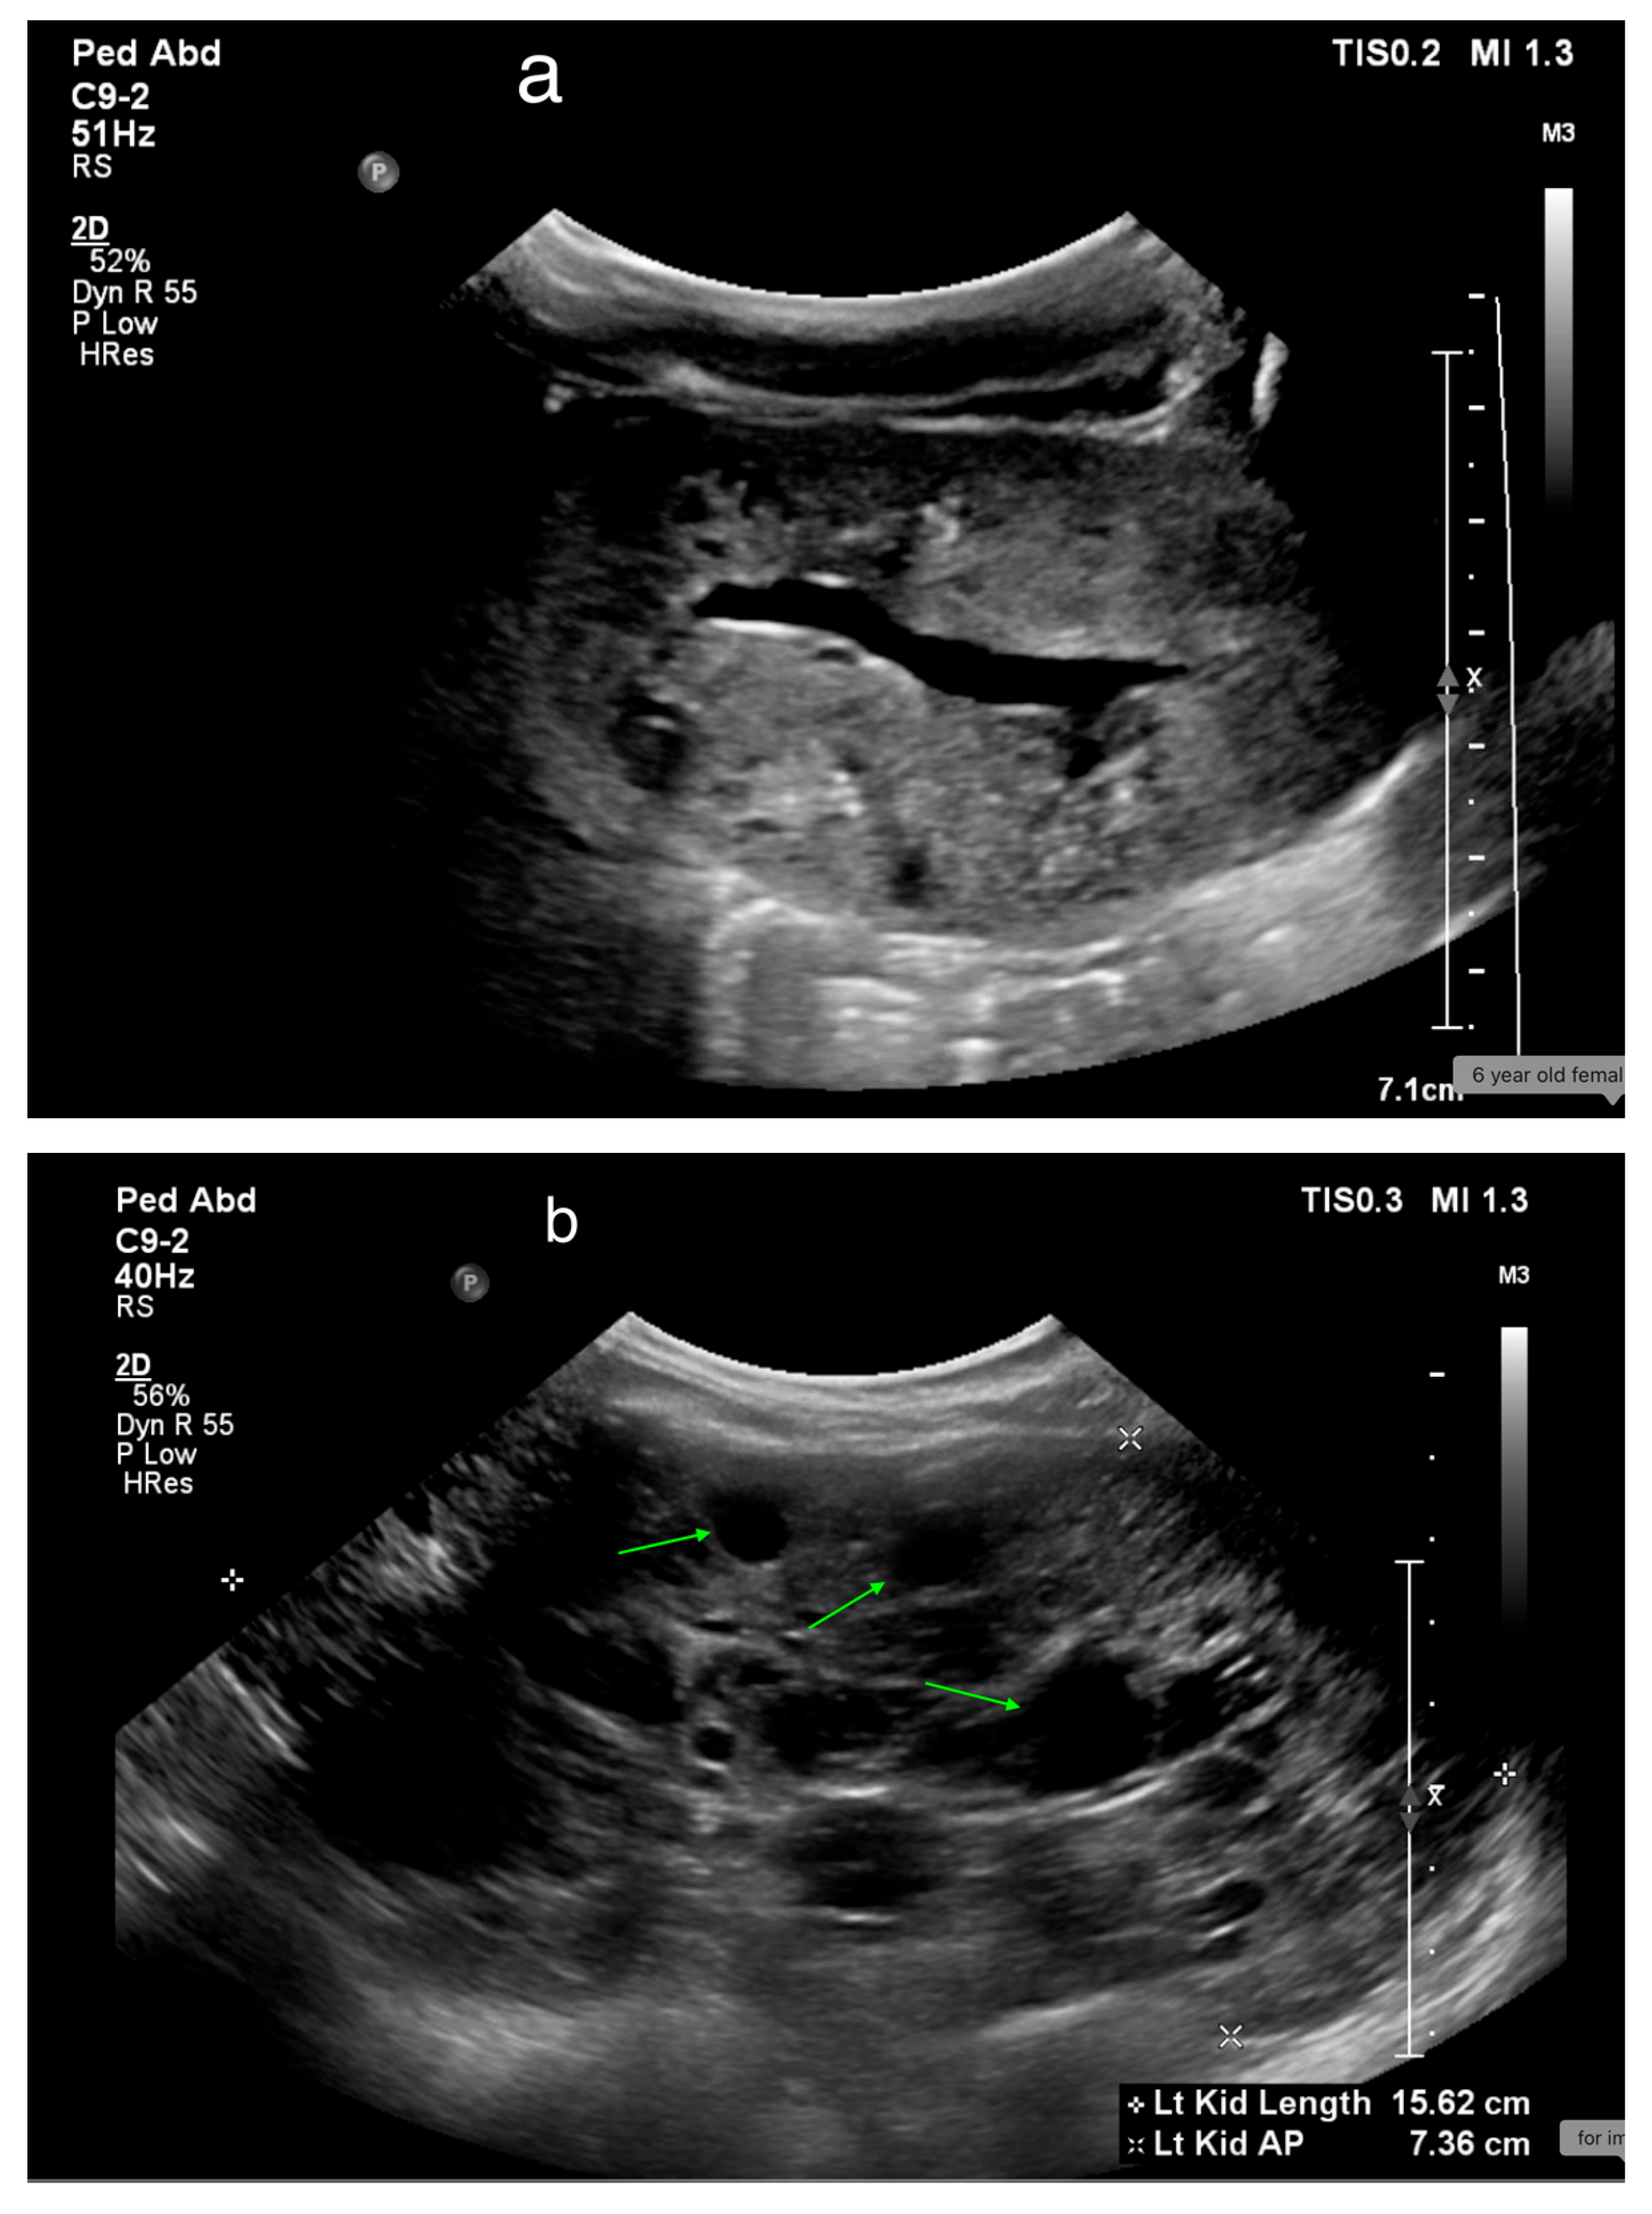

Autosomal recessive polycystic kidney disease (ARPKD) presents with a broad clinical spectrum, from severe perinatal forms to minimal renal disease with dominant hepatic fibrosis. Ultrasound (US) is the initial diagnostic tool, typically showing enlarged, echogenic kidneys with poor corticomedullary differentiation. Microcysts are not visible on US, but macrocysts may be seen in older children (Figure 18) [65,66,67].

Figure 18. (a) ARPKD in a 5-day-old male identified by enlarged, echogenic kidneys with poor corticomedullary differentiation, without visible renal cysts. (b) A 6-year-old female with ARPKD, presenting with significantly enlarged kidneys and macrocysts (highlighted by green arrows).

Medicina 61 00696 g018